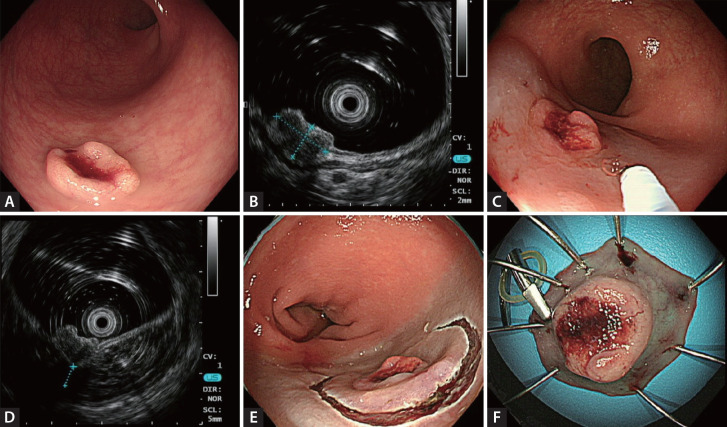

背景/目的:本研究旨在评估微型探针内镜超声(mEUS)联合粘膜下生理盐水注射(SSI-mEUS)评估结肠直肠上皮下病变(SELs)内镜可切除性的可行性和结果。方法:回顾性分析2020年1月至2023年12月391例SELs患者(364例)的医疗记录,并根据使用的方法将其分为无EUS、仅meus和SSI-mEUS组。为了比较SSI-mEUS与其他组之间的变量,将无EUS组和仅meus组合并为无SSI-mEUS组。SSI-mEUS组在生理盐水注射后通过超声测量粘膜下垫层厚度。回顾性分析治疗结果和组织学诊断。结果:无EUS组共切除病变210例,仅meus组23例,SSI-mEUS组125例。SSI-mEUS组的平均SEL大小大于非SSI-mEUS组(6.8±2.6 mm vs. 4.9±2.6 mm, p < 0.001)。SSI-mEUS组110个肿瘤病灶中有107个(97.3%)实现R0切除术,而非SSI-mEUS组176个肿瘤病灶中有159个(90.3%)实现R0切除术(p = 0.046)。未使用si - meus是导致深切边缘不确定或阳性的唯一因素(优势比3.45,95%可信区间1.19-13.40,p = 0.021)。结论:对于结直肠SELs,包括那些在常规内镜检查中出现升高不足的SELs, SSI-mEUS能够客观评估内镜切除的可行性,并可以预测实现安全和完全切除的高可能性。

Background/aims: This study aimed to evaluate the feasibility and outcomes of mini-probe endoscopic ultrasound (mEUS) followed by submucosal saline injection (SSI-mEUS) for assessing the endoscopic resectability of colorectal subepithelial lesions (SELs).

Methods: From January 2020 to December 2023, the medical records of 391 SELs (364 patients) were retrospectively reviewed and categorized into no EUS, mEUS-only, and SSI-mEUS groups according to the procedure used. To compare variables between the SSI-mEUS and other groups, the no EUS and mEUS-only groups were combined into the non-SSI-mEUS group. In the SSI-mEUS group, submucosal cushion thickness was endosonographically measured after the saline injection. Treatment outcomes and histological diagnosis were retrospectively reviewed.

Results: A total of 210 lesions in the no EUS group, 23 in the mEUS-only group, and 125 in the SSI-mEUS group were endoscopically resected. The mean SEL size was larger in the SSI-mEUS than in the non-SSI-mEUS group (6.8 ± 2.6 mm vs. 4.9 ± 2.6 mm, p < 0.001). R0 resection was achieved in 107 of 110 neoplastic lesions (97.3%) in the SSI-mEUS group vs. 159 of 176 neoplastic lesions (90.3%) in the non-SSI-mEUS group (p = 0.046). Not using SSI-mEUS was the only factor associated with indeterminate or positive deep resection margins (odds ratio 3.45, 95% confidence interval 1.19-13.40, p = 0.021).

Conclusion: For colorectal SELs, including those that appear insufficiently elevated during conventional endoscopy, SSI-mEUS enables an objective assessment of the feasibility of endoscopic resection and can predict a high likelihood of achieving a safe and complete resection.